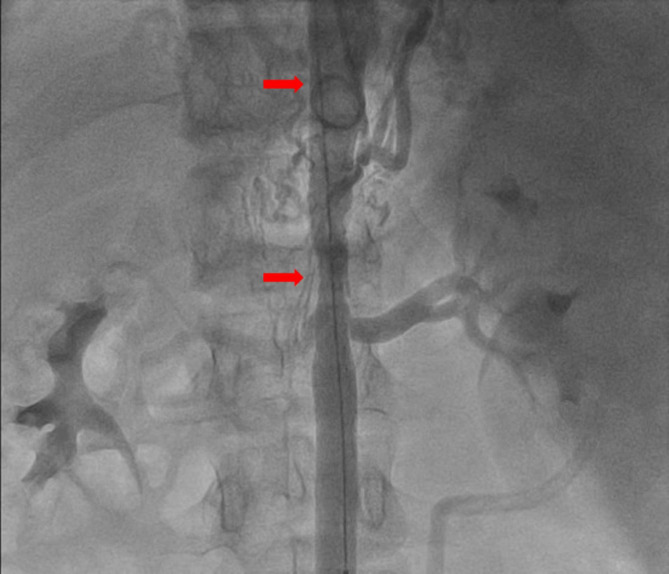

Case presentation: A 14-year-old male presented with a two-year history of refractory hypertension (peak:190/110mmHg) and exertional dizziness. Thoracoabdominal computed tomography angiography (CTA) revealed a focal coarctation (minimum luminal diameter: 4.2 mm, representing 70% stenosis) extending from the celiac artery origin to the superior mesenteric artery origin, without significant collateralization. Digital subtraction angiography (DSA)-guided balloon angioplasty (10 × 40 mm) resulted in a significant reduction of the transcoarctation pressure gradient from 45mmHg to 8mmHg, achieving normotension (120/80mmHg). At six-month follow-up, a 161% increase in aortic luminal diameter (to 11 mm) was observed, accompanied by complete regression of left ventricular hypertrophy (LVH), as evidenced by a decrease in interventricular septal thickness from 12 mm to 9 mm.

背景:先天性局灶性腹主动脉缩窄(CAAC)是一种罕见的血管畸形,常被误诊为中主动脉综合征(MAS)。管理CAAC的一个重大挑战,特别是在年轻人中,是在适应血管生长和发育的同时解决缩窄问题。本病例强调了多学科合作和成像引导的无支架球囊血管成形术在保持血管生长潜力方面的价值。病例介绍:一名14岁男性,有2年难治性高血压病史(峰值:190/110mmHg)和运动性头晕。胸腹ct血管造影(CTA)显示局灶性狭窄(最小管腔直径4.2 mm,狭窄70%),从腹腔动脉起源延伸至肠系膜上动脉起源,无明显侧支。数字减影血管造影术(DSA)引导的球囊血管成形术(10 × 40 mm)使血管收缩压力梯度从45mmHg显著降低到8mmHg,达到正常血压(120/80mmHg)。在6个月的随访中,观察到主动脉腔直径增加161%(至11mm),并伴有左室肥厚(LVH)的完全消退,室间隔厚度从12mm降至9mm。结论:无支架球囊血管成形术是治疗青少年CAAC的有效策略,既能立即缓解血流动力学,又能促进生长适应性主动脉重构。全面的主动脉造影对青少年难治性高血压的诊断和治疗至关重要。